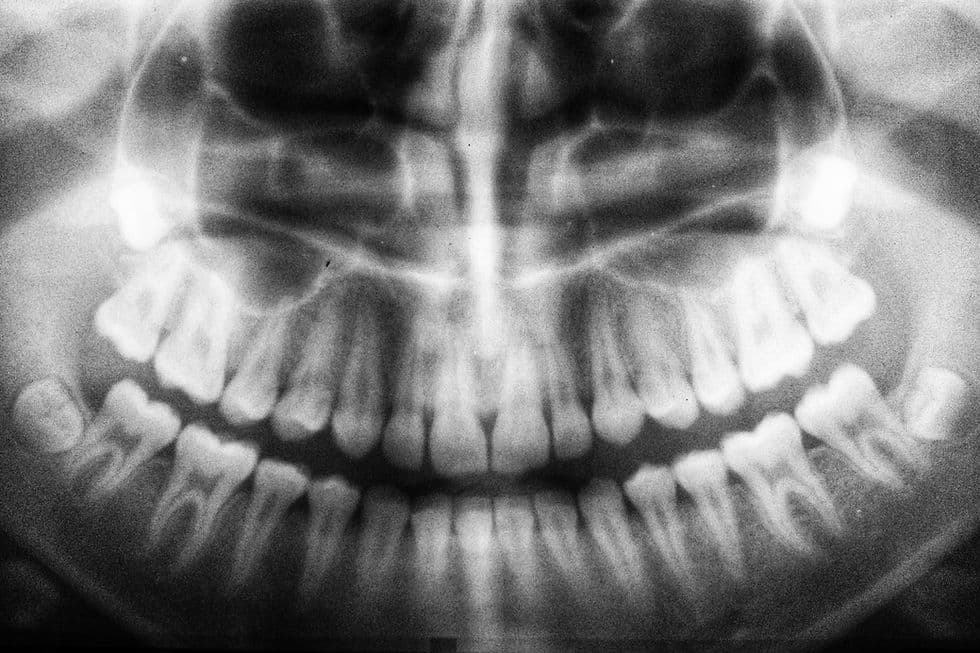

Dental Exams & X-Rays

Regular checkups enable us to identify signs of decay, gum disease, or other issues before they become more severe. Digital X-rays provide a clear and detailed view of what's happening below the surface.